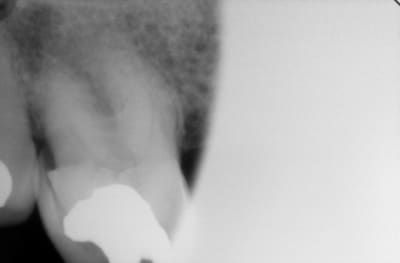

j'ai une retro de la 16 mais elle est pourrie, on voit pas bien...

J'ai pas réussi à avoir mieux que l'image que je vais joindre avec le message.

Tu ne m'as pas dit ce que tu pensais de la 15...

En bouche la frucation commence à apparaitre en V...

donc je pense que c'est mort...

17: racines divergentes, aucune mobilité. Asymptomatique. Pulpe rétractée. Perte de substance importante. Fortement égressée. Le patient n'a pas de parodontite, il a perdu 1 mm d'os en 50 ans. Dent indestructible, elle continuera à égresser jusqu'à toucher la muqueuse en bas et restera immobile tant qu'il restera un peu d'os autour des apex.

Tu dis que tu vois la furcation en vestibulaire mais sur la radio la furcation est encore fermée par de l'os.